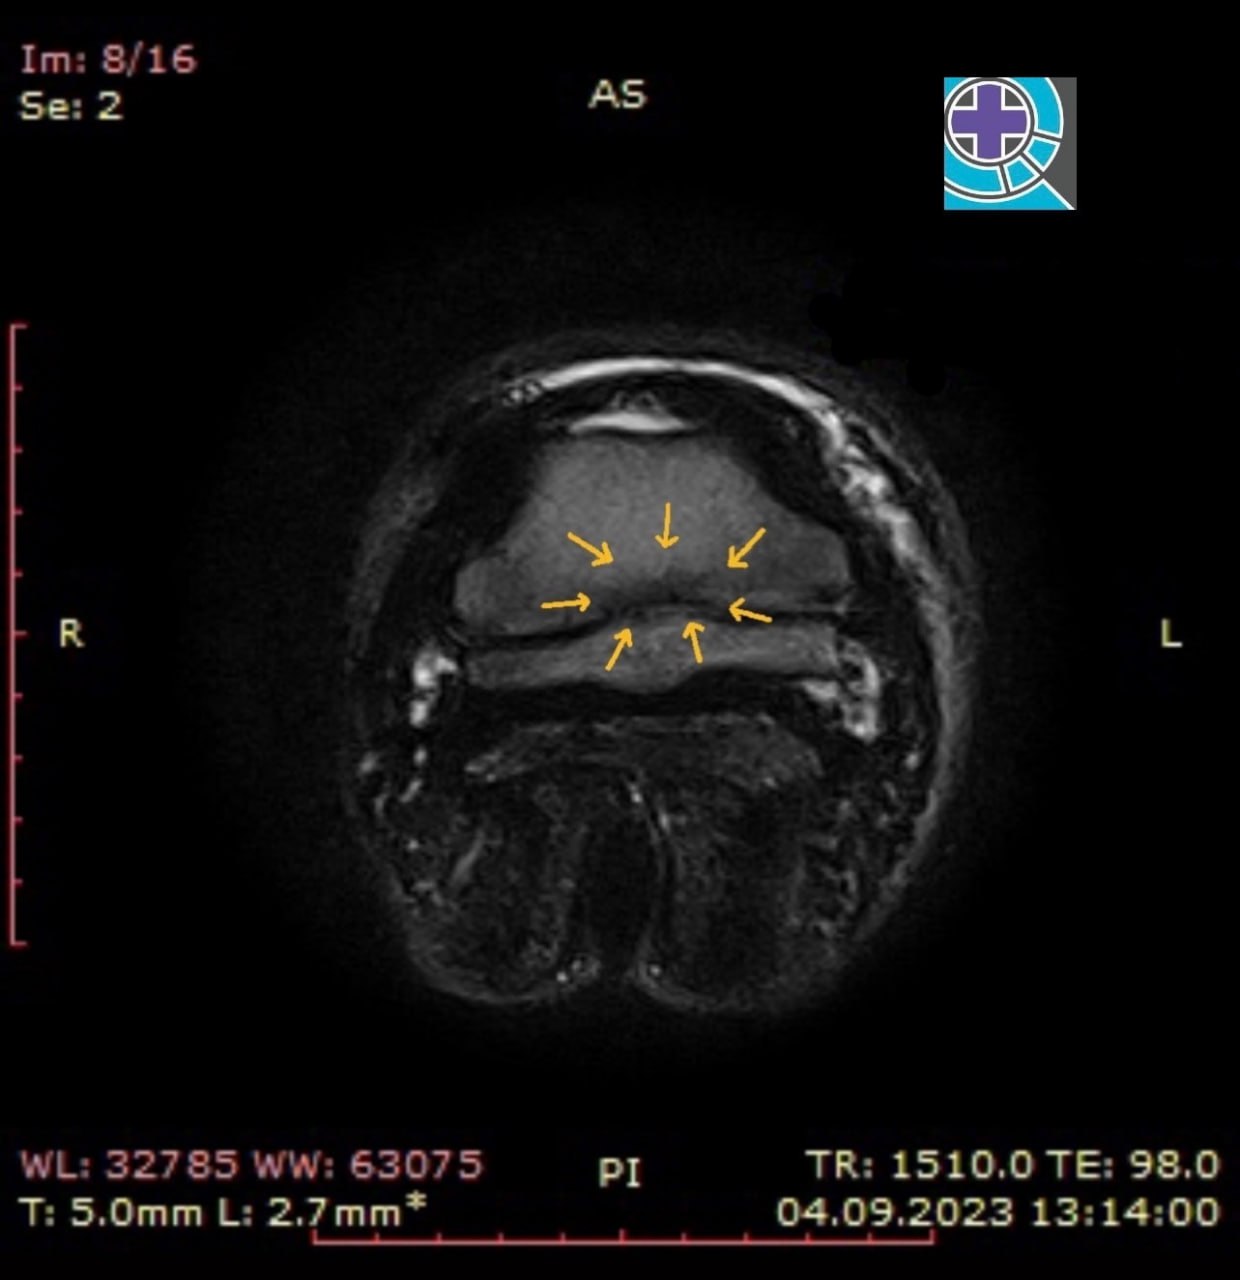

МРТ-исследование: разлитой синовит копытного сустава, отек копытной кости по месту крепления медиальной коллатеральной связки, в Т2 режиме структуры медиальной коллатеральной связки с гиперинтенсивным сигналом.

ДИАГНОЗ: энтезопатия медиальной коллатеральной связки копытного сустава;

артрит копытного сустава.

После МРТ-исследования были даны рекомендации: внутрисуставные инъекции,

курс системных препаратов, шаговая нагрузка в течение 2-х месяцев.

Далее повторный осмотр.